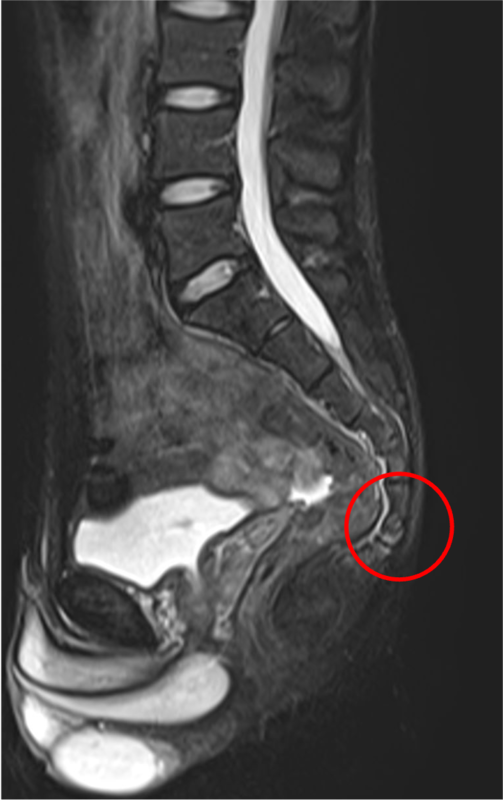

MRI画像

赤く囲んだ部分に痛みが出現している。

尾骨部周囲が白く映り、炎症が起きている。